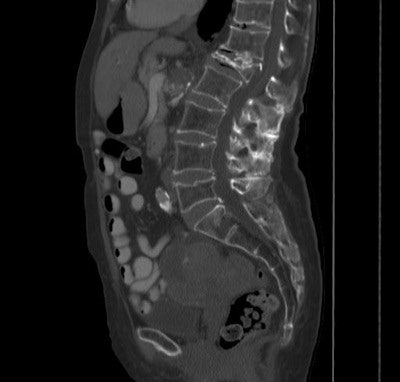

The study evaluated bone mineral density from existing CT scans compared with existing DEXA data in a smaller patient population. The study focused on the L1 vertebrae because it is easily identifiable as the first nonrib-bearing vertebra on thoracic and abdominal scans, Pickhardt said, adding that levels L1 through L5 all were evaluated and showed little variation.

Along with the conventional DEXA exams, CT bone mineral density was measured by choosing a region of interest over vertebral trabecular bone, and measuring Hounsfield units, being careful not to exclude areas that might distort the reading.

Thus, DEXA results applied across the range of CT attenuation results were used to set thresholds that would yield either the 90% sensitivity or 90% sensitivity outcome, or a balance between the two when needed to distinguish osteoporosis from osteopenia. Specifically, an attenuation threshold of 160 HU or less was 90% sensitive, and a threshold of 110 HU was more than 90% specific for distinguishing osteoporosis from osteopenia and normal bone mineral density, the group reported.

CT attenuation values were significantly lower at all vertebral levels for patients with osteoporosis at DEXA (p < 0.001) at the L1 level. Positive predictive values for osteoporosis were 68% or greater at CT attenuation thresholds less than 100 HU; negative predictive values were 99% at thresholds greater than 200 HU, the group reported.